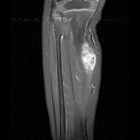

N.L. - 3 year old female with right calf mass; she denies any pain, her mother noticed it four weeks ago